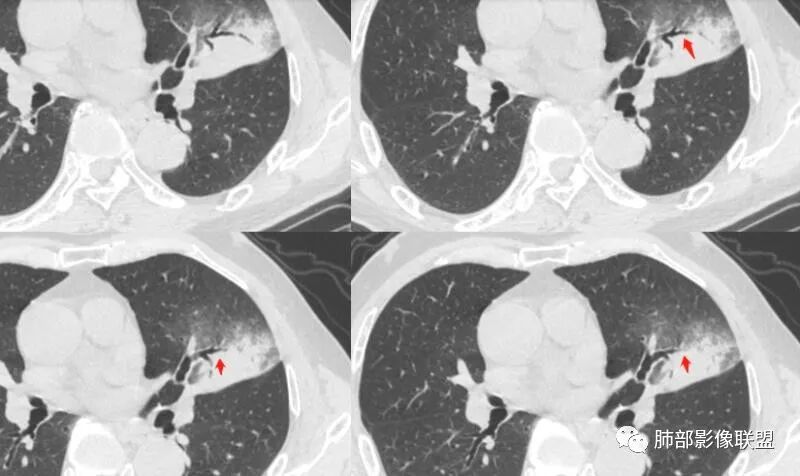

我标示一下,尖后段搭到一部分,前段也占了一点点。

主体在舌段

有占位效应吗?

有,斜裂局部膨隆

边缘膨隆,叶间裂有局部膨出下坠

有膨隆+收缩

支气管?

支气管外面堵了,近端有扩张

中远端堵塞,堵塞端圆钝

炎性? 肺炎型肺癌待排

空洞内侧软组织肿块,比较支持恶性吧

这个空洞的性质很重要,对最后诊断结果影响大,如果中间没有曲菌球,那就是偏心空洞,指向恶性,如果是曲菌球引起的新月形改变,那就不一定。至于到底是曲菌球还是偏心空洞,需要仔细看看强化情况。